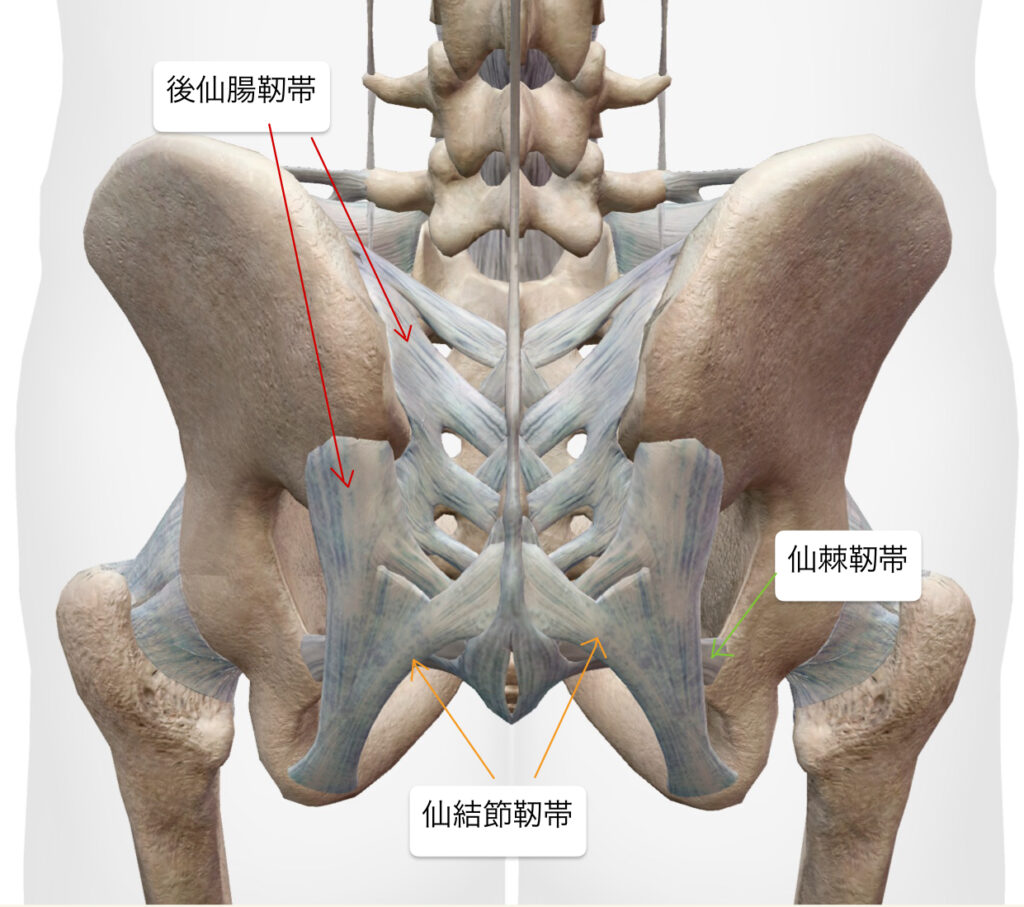

・超音波エコーで観察したところ、腰椎5番目・仙骨1番の椎間関節と仙腸関節の靭帯周囲にファシアの重責がみられた。

・坐骨神経痛の原因が腰椎5番目の神経根周囲の可能性があったため、エコーガイド下L5/S1神経根と後仙腸靭帯に対しエコー下鍼施術、鍼通電を行った。